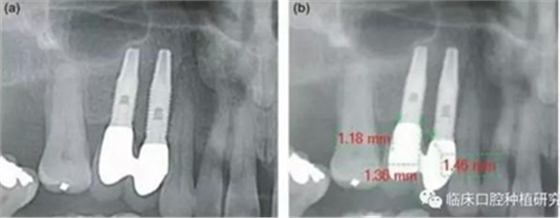

因而,該研究對隨訪達5年以上的牙列缺損種植修復患者,進行了觀察性縱向回顧性研究。通過影像學資料對比種植體周圍骨吸收和牙周骨吸收,對其潛在危險因素,如修復體設(shè)計、口腔衛(wèi)生、植體規(guī)格也進行了研究。單變量統(tǒng)計分析結(jié)果發(fā)現(xiàn),性別、種植體系統(tǒng)、拔牙原因、聯(lián)冠修復、種植體平臺和修復體間水平距離與種植體周圍骨吸收有顯著相關(guān)性。多變量統(tǒng)計分析結(jié)果發(fā)現(xiàn),性別、種植體系統(tǒng)、拔牙原因、聯(lián)冠修復、種植體平臺和修復體間水平距離與種植體周圍骨吸收同樣具有顯著相關(guān)性。其結(jié)果認為種植體平臺和修復體間水平距離對種植體周圍骨吸收負向影響最大,且這一距離適宜在3.3 mm-6 mm。若超出此范圍,則對種植體周骨吸收不再有影響,但外展隙會逐漸增大,菌斑堆積增多。